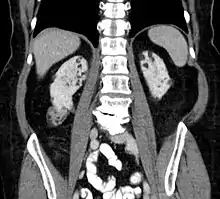

Kidneys

Between 60 and 80% of TSC patients have benign tumors (once thought hamartomatous, but now considered true neoplasms) of the kidneys called angiomyolipomas frequently causing hematuria. These tumors are composed of vascular (angio–), smooth muscle (–myo–), and fat (–lip-) tissue. Although benign, an angiomyolipoma larger than 4 cm is at risk for a potentially catastrophic hemorrhage either spontaneously or with minimal trauma.